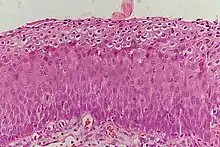

Cervical intraepithelial neoplasia (CIN), spanning a bit more than 2/3 of the thickness of the cervical epithelium.